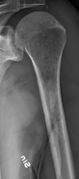

Femur with multiple myeloma lesions.